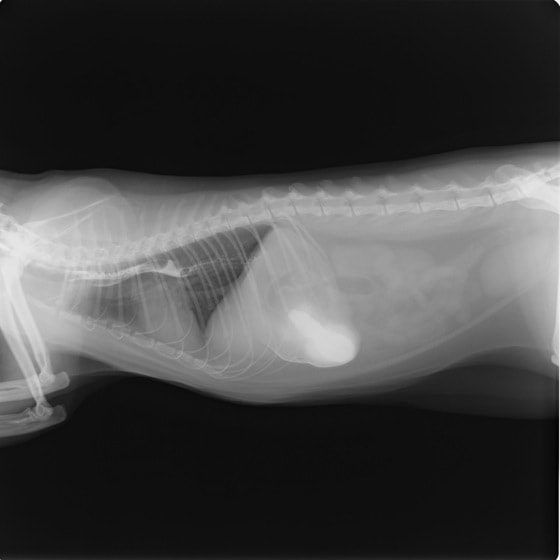

11歳 ミニチュア・ダックス 去勢オス

主訴:焼き鳥の竹串を食べたとの事で来院しました。元気・食欲は問題なく、嘔吐などの症状もありませんでした。便にも竹串が1/3程でているとの事でしたが、全ての竹串が出ていないため、内視鏡検査を実施致しました。

内視鏡検査所見:胃内に竹串の先端部分が残っていたため、異物鉗子にて摘出しました。胃内は、全体的に炎症を伴い、出血している部位も確認されました。摘出後は、胃粘膜保護薬・プロトンプインヒビター(胃薬)の内服2剤ならびに食事療法により経過は良好です。